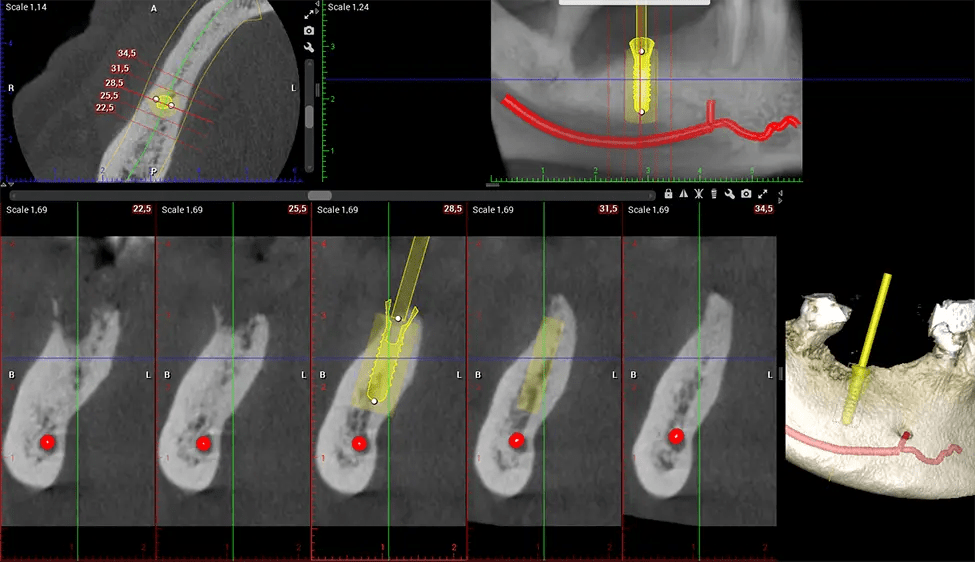

When paired with extractions, dental implant placement, or bone grafting, CBCT technology can provide you with a quicker and much more comfortable experience. This is because the 3D image provides a more detailed picture of your entire oral cavity, allowing your dentist to walk you through each step of the process before it occurs. This often helps patients feel more prepared and comfortable overall, especially if they have had a traumatic experience with past dental treatments.

After the scanning process, the captured X-ray images are processed by the CBCT software, which applies algorithms to reconstruct a detailed 3D image of the scanned area. The software compiles these individual X-ray images and creates a digital 3D representation of the patient’s anatomy. The reconstructed 3D CBCT image can be viewed and analyzed by the dentist or radiologist. This image can be manipulated, rotated, and zoomed in or out to examine specific structures and evaluate the patient’s condition.

Planmeca Viso G7 CBCT ( Cone Beam CT Scan ) is designed to surpass the demands of industry leaders, specialists, and large institutions. It’s has a large ø25×30 cm sensor with four built-in cameras. It can capture unlimited volume sizes from a ø3×3 cm to a ø30x30cm volume capturing the skullcap through C7 on the cervical spine. The Planmeca Viso G7 offers the industry’s largest single volume scan of ø30×19 cm. It’s poised to handle advanced imaging modalities such as Planmeca ProFace® and Planmeca 4D™ Jaw Motion technology. The occipital head support allows an unimpeded view of facial tissue.

Planmeca is the only manufacturer clinically proven to dramatically reduce patient radiation without sacrificing image quality. Planmeca Ultra Low Dose™ achieves an average reduction in dose of 77% without a statistical reduction in image quality allowing doctors to incorporate 3D imaging into routine protocols with effective patient radiation often lower than 2D intraoral imaging. This increases patient care, allows doctors to diagnose more dentistry, and often earlier in disease progression, than with 2D imaging alone.